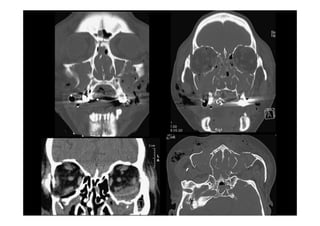

Radiología